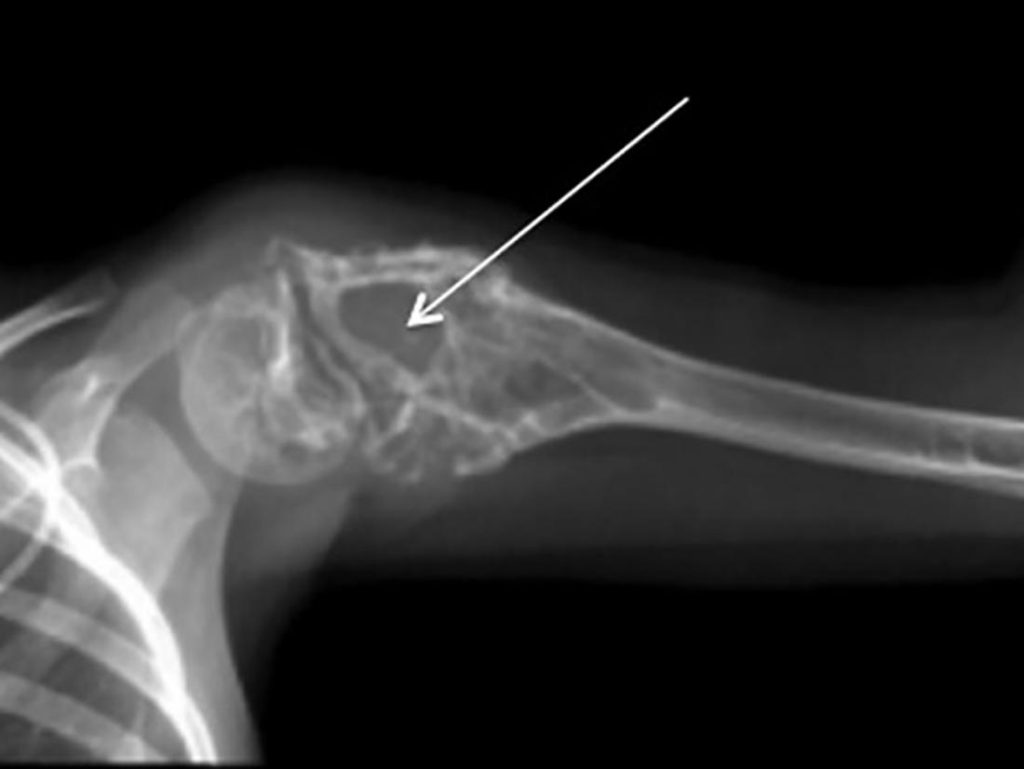

Ewing’s sarcoma is a rare form of cancer that predominantly affects teenagers but can also occur in younger children and young adults. Known also as Ewing's sarcoma or Ewing tumor,...